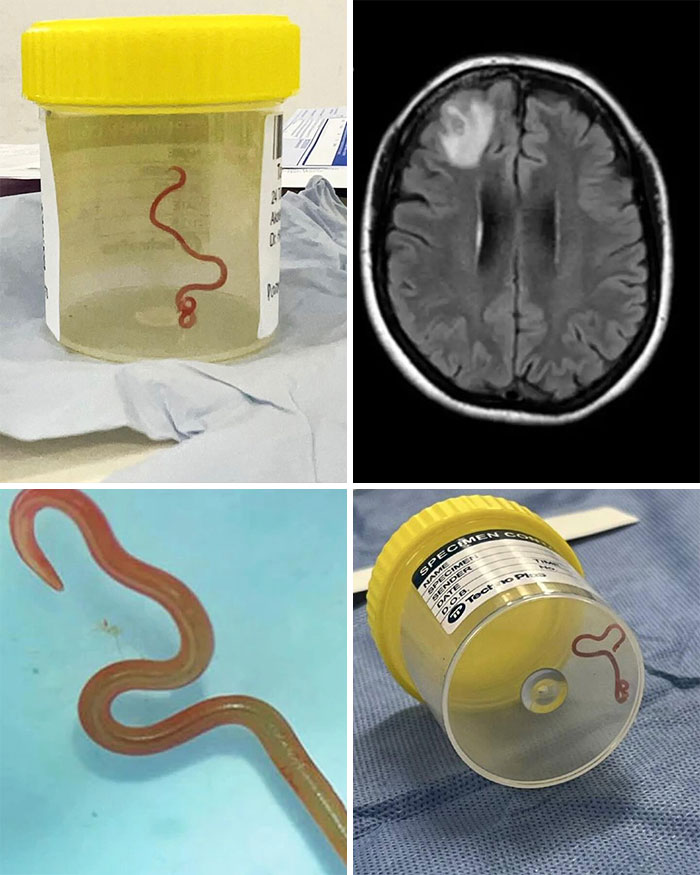

Neurosurgeon Removes Live 8cm Long Worm From Woman's Brain!!

Scientists last month published an unprecedented case, where they found and extracted a live parasitic worm from the brain of a 64-year-old Australian woman.

The neurosurgeon found and removed the parasite with forceps during a biopsy, from within the lesion shown on the MRI (light gray area).

"I used tumor-holding forceps and lifted out something that I definitely was not expecting: a linear, squiggling line, and my junior doctor said, 'is that an artery?', because that's what it looked like. And I said, 'it's not an artery, we're nowhere near any artery!' And I noticed it was moving and I went, 'just get it out of my forceps!' So we rapidly put it in a pathology pot, and it was a vigorously wriggling worm."

Symptomatically, weeks of abdominal pain and diarrhea led to night sweats and a dry cough, but evolved towards problems like forgetfulness and depression, presumably as the worm׳s activities kept affecting different parts of the brain.

The worm was some 8 centimeters (just over 3 inches) long and is a rare parasite called Ophidascaris Robertsi. This is a type of Roundworm (Helminth). This roundworm usually lives in a Carpet Python. The eggs of the worm are around the snakes’ faecal droppings, which infect the grass. This grass containing the eggs, are eaten by small mammals, who are then eaten by the Carpet Python. This is how this worm gets cycled between its two hosts. This woman became an 'accidental host'. She lived near the carpet python habitat and while foraging the native vegetation for cooking, she ingested the worm eggs. The worm developed in her intestine and travelled via blood circulation to her brain.

In response, the body produces inflammation around the worm and as a result, an area of inflammatory tissue or granuloma develops in the brain. Depending upon the affected location, it can cause a multitude of symptoms such as pressure symptoms - headache, vomiting, visual blurring, confusion, altered sensorium, cognitive symptoms - forgetfulness, problems in understanding, calculations, disorientation, seizures and epilepsy - due to irritation of the brain by inflammatory tissue.